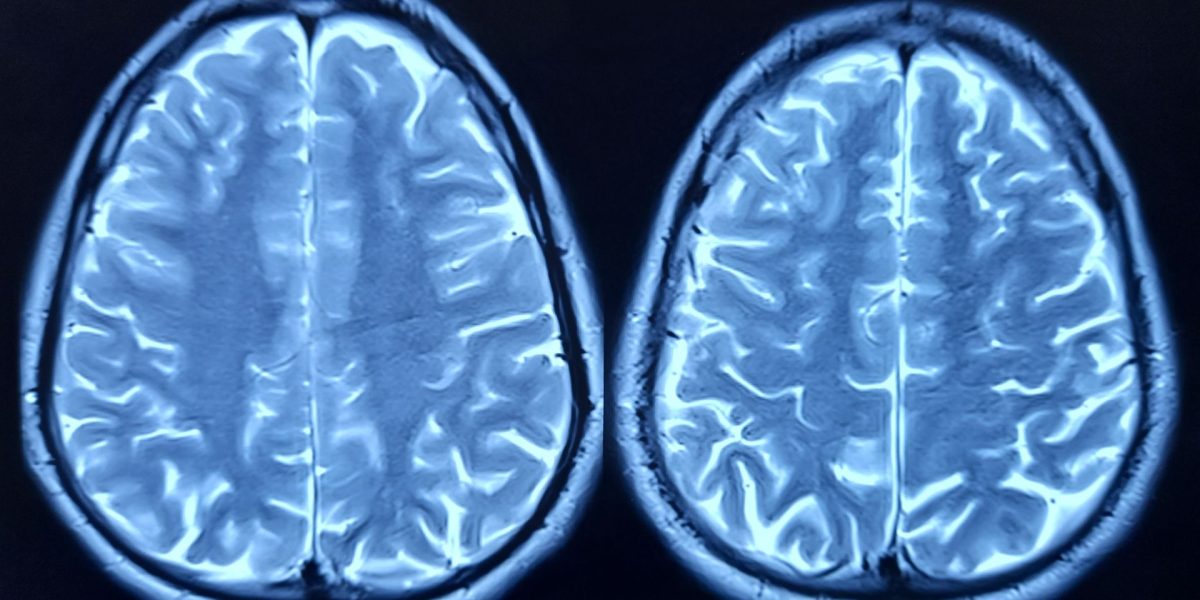

Cercetătorii au identificat o proteină numită FTL1, care ar putea fi un factor cheie în declinul cognitiv asociat cu vârsta. La șoarecii în vârstă, nivelurile ridicate ale acestei proteine au fost corelate cu slăbirea conexiunilor neuronale din hipocamp, o zonă esențială pentru învățare și memorie. Aceste descoperiri sugerează că FTL1 ar putea avea un rol semnificativ în procesul de îmbătrânire cerebrală și că modificări ale nivelurilor acestei proteine ar putea fi o țintă pentru viitoare tratamente. Cercetările au analizat genele și proteinele din hipocampul șoarecilor de diferite vârste și au observat că, odată cu trecerea anilor, nivelurile de FTL1 au crescut considerabil la animalele bătrâne. În același timp, acestea prezintă o diminuare a conexiunilor neuronale și rezultate defavorabile în testele cognitive, confirmând o prejudecată comună despre declinul mental odată cu înaintarea în vârstă. Punctul central al studiului a fost experimentul în care cercetătorii au crescut artificial nivelul de FTL1 la șoarecii tineri. Rezultatele au fost surprinzătoare: animalele au început să prezinte structuri neuronale mai simple și o performanță cognitivă scăzută, asemănătoare cu cea a șoarecilor bătrâni. Acest fapt indică clar influența directă a proteinei asupra funcționării cerebrale.

Celulele nervoase modificate genetic pentru a produce mai mult FTL1 au dezvoltat rețele mai puțin complexe, cu extensii scurte și simple, reducând astfel capacitatea de comunicare între neuroni. Această modificare structurală face ca funcționarea creierului să fie mai puțin eficientă, explicând și declinul cognitiv observat la șoarecii în vârstă. Interesant este că reducerea nivelului de FTL1 la șoarecii bătrâni a dus la o ameliorare a conexiunilor celulare, precum și la o îmbunătățire a performanței în testele de memorie. În aceste condiții, celulele cerebrale au reușit să își recapete o parte din capacitatea de a comunica, sugerând că procesul de regenerare este posibil dacă nivelurile de această proteină sunt controlate. Saul Villeda, directorul adjunct al Institutului de Cercetare a Îmbătrânirii Bakar din cadrul UCSF, a declarat că aceste rezultate reprezintă o adevărată inversare a deficiențelor cerebrale asociate cu vârsta, subliniind potențialul de dezvoltare a unor terapii specifice pentru combaterea declinului cognitiv.

Pe lângă efectele asupra conexiunilor neuronale, cercetările au arătat că FTL1 afectează și modul în care celulele cerebrale utilizează energia. La șoarecii bătrâni, nivelurile crescute ale proteinei au încetinit metabolismul celular în hipocamp. Experimentele efectuate cu compuși care stimulează metabolismul au demonstrat că pot preveni aceste efecte negative și, în unele cazuri, chiar inversa deteriorarea. Aceste descoperiri sugerează o posibilă cale de intervenție terapeutică, în care reducerea nivelurilor de FTL1 și stimularea metabolismului celular s-ar putea combina pentru a îmbunătăți funcționarea creierului în cazul persoanelor în vârstă. Villeda afirmă că aceste rezultate deschid noi posibilități pentru tratarea sau prevenirea declinului cognitiv asociat cu îmbătrânirea. Pentru moment, cercetările continuă pentru a înțelege mai bine mecanismele exacte prin care FTL1 influențează structura și funcția creierului. În 2023, studiile clinice preliminare se află în faza de planificare, urmând să exploreze modul în care aceste descoperiri pot fi aplicate în terapii umane. Sursa: DescoperaO proteină care pare să pună în pericol funcționarea creierului odată cu îmbătrânirea